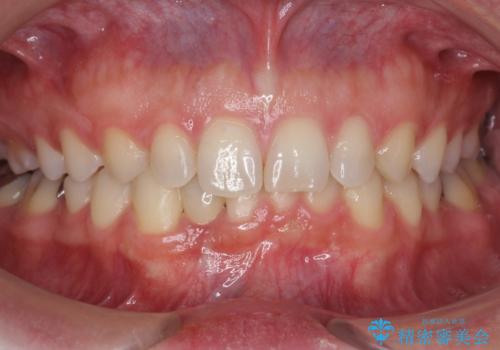

前歯が気になる 大人のマウスピース矯正 矮小歯を整える